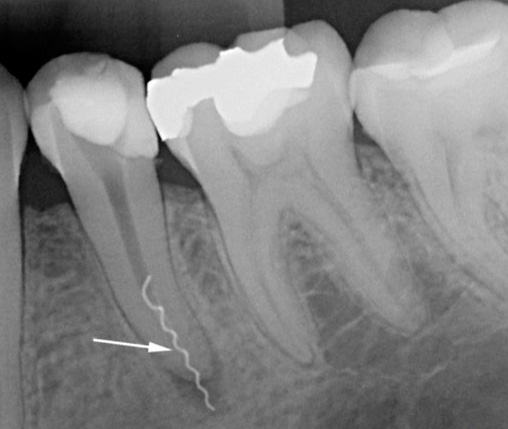

- Strumento rotto nel canale. In questo caso, la complicazione sorge a causa del lasciare un pezzo di uno strumento dentale nel canale con una fonte di infezione - un "nervo" infiammato o con batteri non lavati fuori dal canale. In futuro, questo spesso porta a dolore dopo aver riempito i canali dentali - immediatamente o dopo alcune settimane (a volte anni).

Ho studiato dettagliatamente l'immagine del dente depilato, ma non fornisce tutte le risposte alle domande, ma solo un'idea approssimativa di riempimento dei canali. Si sospettava che alcuni canali non fossero sigillati a un restringimento fisiologico. Per concretizzare questo fatto e cercare un canale aggiuntivo (che non è stato possibile rilevare), è necessario effettuare un tiro di mira di questo particolare dente. Questa sarà una versione ingrandita in cui puoi considerare tutto. L'opzione migliore potrebbe essere le immagini su un visiografo in diverse proiezioni. Tuttavia, la radiografia di contatto "film" può essere appropriata.